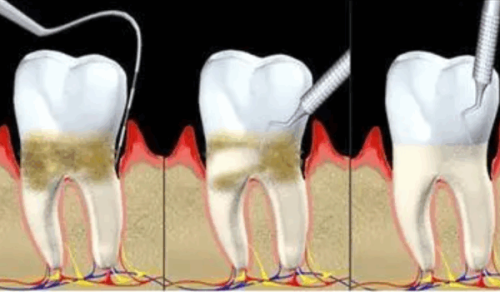

合肥美奥口腔医院成立以来,一直致力于为患者提供优质、效率高、舒适的口腔医疗服务。医院环境优雅,设备精良,拥有一支专精的医疗团队。医院开展的项目包括牙齿矫正、种植牙、牙齿美白、牙周治疗等多个领域,能够满足不同患者的需求。下面为大家附上一份简单的价格表(仅供参考):